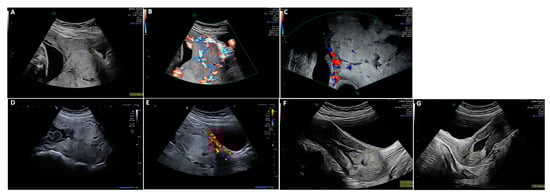

All patients with PAS presenting at our center between 2005 and 2021 were included. The outcome of 19 patients has already been published, focusing on physical, mental, and reproductive sequelae after the treatment of PAS [31,34]. Antenatal diagnosis of PAS was made using 2D ultrasound, color Doppler, and transvaginal ultrasound [35,36]. Ultrasound criteria included loss of the clear zone or decidua, partial or complete absence of the myometrium layer, sub-placental lacunae, a sudden break-off in the outline of the calcifications characteristic for third-trimester placental basal plates, increased vascular perfusion between the uteroplacental interface reaching the uterine serosa, bladder wall interruption, placental bulge, and exophytic mass hypervascularity (Figure 1) [8,35,36,37,38].

Figure 1.

(A–C) PAS in 34 + 0 weeks of gestation with loss of decidua, bladder wall interruption, placental bulge, and exophytic mass hypervascularity. (D,E) Placenta in situ on day 13 after CS with persistent bladder wall interruption. (F) Placenta in situ on day 63 after CS with a diameter of about 3.5 cm, well separated from the uterine wall, without perfusion. (G) Day 122 after CS; fluid-filled uterine cavity surrounded by a hyperechogenic rim.